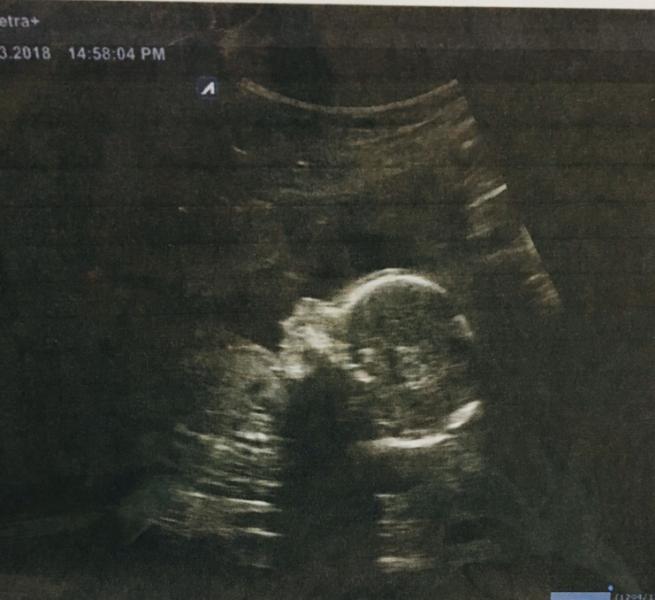

Как любой женщине мне очень хотелось лялю 😊😊😊 Мне было все равно кто, мальчик, девочка, неважно, я знала чт...